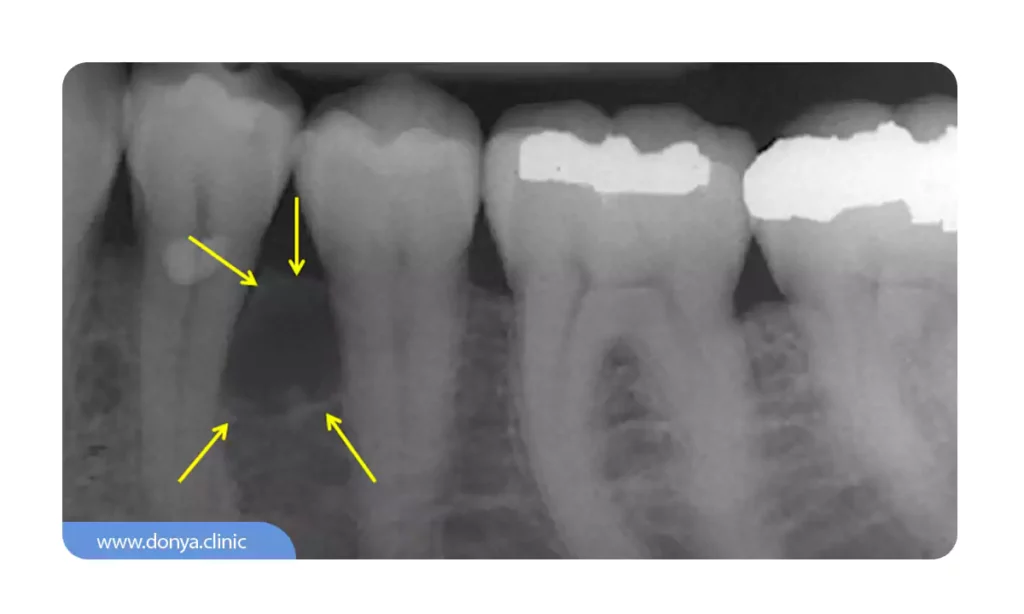

کیست های رادیکولار (Radicular Cysts)

کیست های رادیکولار که به عنوان کیست پری آپیکال نیز شناخته می شوند، شایع ترین نوع کیست دندان هستند. آنها در نتیجه عفونت یا التهاب در پالپ دندان ایجاد می شوند که معمولاً در اثر پوسیدگی دندان یا ترومای درمان نشده ایجاد می شود.